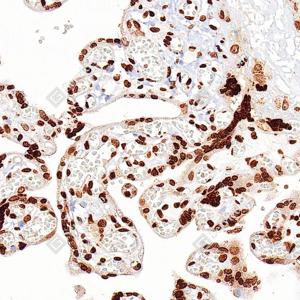

| IHC检测Histone H1. 5蛋白(货号 GB150208). 样品: 人胎盘, 4%多聚甲醛 (货号G1101) 固定12-24小时. 抗原修复: 抗原修复仪(货号 ARI-4),柠檬酸抗原修复液(干粉, pH 6.0) (G1201), 高压锅均匀喷气计时2分钟. —抗: 1: 1000稀释, 4℃ 孵育过夜. 二抗: S-vision免疫组化多聚二抗(山羊抗小鼠), 即用型(货号G1301), 室温孵育20分钟. |